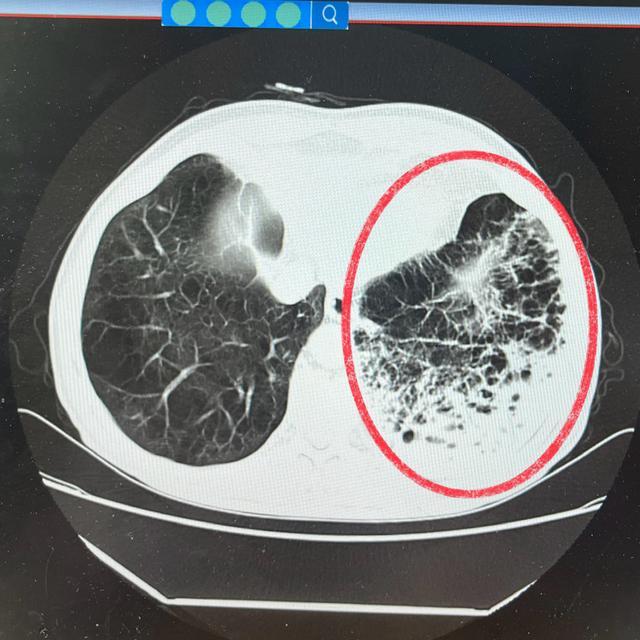

(入院时肺部CT)

入院后,肺病科覃友贵主任对其进行了全面而细致的评估,他明确指出,多年的肺部疾病,唐爷爷的肺功能已处于非常脆弱状态,再加上这次起病急、感染又如此严重,极有可能导致病情急剧恶化,如果引发呼吸衰竭等严重并发症,可能危及生命!